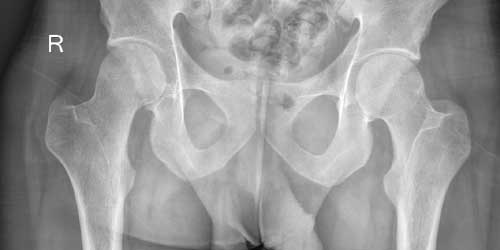

Sakrum omurga ve pelvis (leğen kemiği) arasında bağlantıyı sağlayan kendine has anatomik yapıya sahip ve içinde sakral sinir (S1-4) köklerini bulunduran, beş farklı kemikten (S1-5) oluşan özel bir kemiktir.

Nedeni ve kaynaklandığı doku tam olarak bilinmemektedir. Sakrum omurgada tipik yerleşim yerlerinden biridir. Dev hücreli kemik tümörü lokal agresif dediğimiz bulunduğu kemikte harabiyete neden olan ve ameliyat sonrası tekrarlamaya (nüks) yatkın olan bir tümördür. Genellikle ağrı ve şişlik ile hekime başvururlar ancak sakrum yerleşimlilerde sinir hasarı bulguları (uyuşma, karıncalanma, güçsüzlük, idrar, gaita ve seksüel fonksiyon bozuklukları) gelişebilir. Şikayetler çok tipik olmadığı için uzun süreli var olabilir ve diğer tanılarla (bel fıtığı, sakroileit vs) karıştırılabilir. Hastalar genellikle şikayetlerinin zamanla arttığını ifade ederler. Sakrum dev hücreli kemik tümörü yerleşim yeri nedeniyle (barsak gaz gölgeleri) direk grafi (röntgen) de bulgu vermeyebilir ve atlanabilir. Tomografide tümörün yerleşim yeri, sınırları ve kemik hasarının boyutu, ilaçlı (kontrastlı) MR’da ise kemiğin dışındaki yumuşak doku komponenti ve sinir kökleri daha ayrıntılı ortaya konur. Dev hücreli kemik tümöründe tanı klinik ve radyolojik değerlendirme sonrası yapılacak biyopsi işlemi ile kesinleştirilir. Biyopsi işlemi sıklıkla lokal anestezi altında görüntüleme eşliğinde (skopi ya da tomografi) özel iğneler (Jam Shidi) yardımıyla kapalı olarak gerçekleştirilir. Biyopsi işlemini yapacak olan ortopedi hekiminin ve örneklerin incelemesini yapacak olan patoloji hekiminin kemik ve yumuşak doku tümörleri alanında deneyimli olması önem arz eder. Dev hücreli kemik tümörü iyi huylu olmasına rağmen çok nadir de olsa (%3-5) maalesef akciğere sıçrama (metastaz) yapabilmektedir. Bu nedenle tanısı kesinleşen hastanın öncelikle akciğer metastazı açısından taraması (Toraks BT) yapılmalı. Dev hücreli kemik tümörünün asıl tedavisi tümörün cerrahi olarak çıkarılmasıdır. Bunun için küretaj dediğimiz yöntemle tümör kemikten kazınarak çıkarılır. Nüks ihtimalini azaltmak için rutin olarak adjuvan (koter, burr, fenol, alkol, hidrojen peroksit, sıvı azot vs) yöntemlerle agresif küretaj uygulamaktayız fakat sinir köklerinin yakınlığı nedeniyle bu işlemi sakrumda sınırlı olarak yapabilmekteyiz. Bu nedenle sakrum yerleşimli tümörlerde nüks ihtimali ekstremite (kol, bacak) yerleşimlilere göre maalesef daha yüksektir. Tümörün çıkarılması sonrası oluşan boşluk sıklıkla kemik çimentosu ile doldurulur. Tümörün ya da ameliyatın neden olduğu kemik zayıflığı (stabilite yetersizliği) gelişen hastalarda farklı yöntemlerle güçlendirme (fiksasyon) işlemi yapabilmekteyiz. Ayrıca bu bölgedeki tümörler kanamaya daha yatkın oldukları için ameliyat öncesi embolizasyon (anjio ile tümörü besleyen damarı tıkama) önerilmektedir. Denosumab dev hücreli kemik tümörlerinde kullanılan bir çeşit kemik güçlendirici bir ilaçtır. Sakrum yerleşimli dev hücreli tümörlerde özellikle kemik harabiyetinin ileri boyutta olduğu, ameliyatın çok riskli ve yapılamayacak durumda olduğu ve nüks vakalarda denosumab tedavisine başvurabilmekteyiz. Denosumab tedavisinin ne kadar süreyle kullanılması gerektiği tartışmalıdır ve hastaya göre karar verilmelidir. Denosumab tedavisi kesilen hastalarda tümörün tekrar etme riski vardır. Benzer şekildeki durumlarda radyoterapi diğer bir tedavi yöntemidir ancak her iki yönteme de seçili vakalarda çok dikkatli bir değerlendirme sonrası başvurulmalıdır. Çünkü her iki yöntem sonrası iyi huyludan kötü huyluya (malign dev hücreli tümör) dönüşüm riski vardır. Sakrum dev hücreli kemik tümörlerinde nadiren kısmi (parsiyel) sakrektomi uygulamaktayız. Tedavi edilen hastalar nüks açısından ameliyat sonrası belirli aralıklarla uzun yıllar yakın takip edilmelidir.

Notokord kalıntıdan kaynaklı yavaş seyirli (ortaya çıkmasından tanı anına kadar uzun süre geçebilir) kemik kanseridir. Kordoma en sık omurgada sakrum ve boyun bölgesinde yerleşir. Hastalar sıklıkla ağrı ve şişlik ile hekime başvururlar. Komşuluk nedeniyle sıklıkla bel problemleri (bel fıtığı, daralma vs) ile karıştırılırlar. Çok büyük boyutlu tümörlerde rektumu sıkıştırabildiği için hastalarda kabızlık gelişebilir. Özellikle her iki taraflı ve çok seviyeli sinir basısı olan tümörlerde ayak tabanında uyuşma, karıncalanma, güçsüzlük, idrar ve gaita kontrol bozukluğu ile ve seksüel fonksiyon yetersizlikleri gelişebilir. Bulunduğu lokalizasyondan dolayı (barsak gazlarının gölgelemesi) direk grafi (röntgen) de bir bulgu vermeyebilir ve atlanabilir. Tomografide tümörün yerleşim yeri, sınırları ve kemik hasarının boyutu, ilaçlı (kontrastlı) MR’da ise kemiğin dışındaki yumuşak doku komponenti ve sinir kökleri daha ayrıntılı ortaya konur. Komşu organlarla olan ilişkisi ayrıntılı değerlendirilir ve ameliyat planlaması yapılır. Dev hücreli kemik tümöründe tanı klinik ve radyolojik değerlendirme sonrası yapılacak biyopsi işlemi ile kesinleştirilir. Biyopsi işlemi sıklıkla lokal anestezi altında görüntüleme eşliğinde (skopi ya da tomografi) özel iğneler (Jam Shidi) yardımıyla kapalı olarak gerçekleştirilir. Biyopsi işlemini yapacak olan ortopedi hekiminin ve örneklerin incelemesini yapacak olan patoloji hekiminin kemik ve yumuşak doku tümörleri alanında deneyimli olması önem arz eder. Tanısı konulan hastaya metastaz taraması için toraks tomografisi ve vertebra manyetik rezonans görüntüleme (MR) yapılmalıdır. Kordoma kemoterapi ve radyoterapiye dirençli olduğu için asıl tedavisi tümörün temiz sınırlar ile çıkarılmasıdır. Bu amaçla tümörün yerleşim yerine göre tam (total) ya da kısmi (parsiyel) sakrektomi uygulanır. Cerrahi tedaviye uygun olmayan ya da nüks vakalarda karbon ion ya da proton tedavisi uygulanabilir ancak bu iki yöntem de ülkemizde olmayıp yurt dışında belli merkezlerde uygulanabilmektedir ve çok yüksek maliyetlidir.